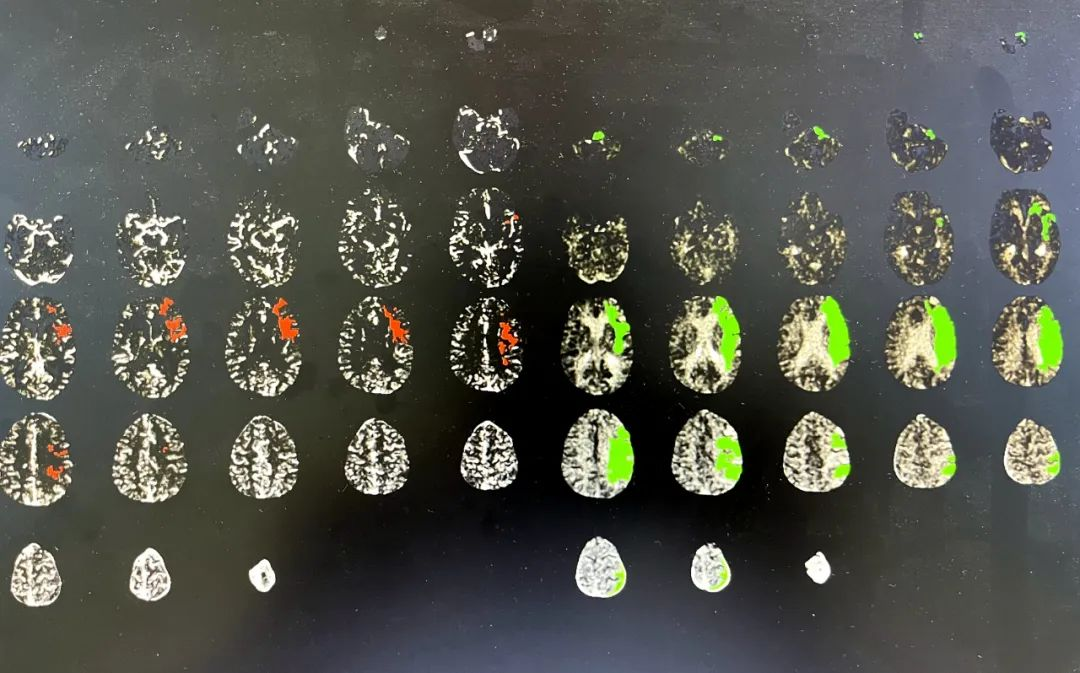

上图为患者溶栓前脑灌注成像结果,红色区域代表脑组织已经坏死,绿色区域代表尚可以挽救的脑组织,脑灌注成像结果综合提示患者仍存在大量可挽救的颅脑组织。

神经内科团队对患者的病情进行充分评估后,考虑患者为“醒后卒中”,仍然有可能存在尚可挽救的缺血脑组织,因此迅速联系影像团队,完成一站式的颅脑CT灌注成像检查。通过人工智能istroke软件系统评估后发现患者“左侧大面积脑梗死合并相应血管供血区域明显缺血半暗带”。经与北京天坛医院专家线上交流评估后,患者符合新项目“注射用重组人TNK组织型纤溶酶原激活剂(rhTNK-tPA,铭复乐)治疗超时间窗(发病4.5-24h)急性大动脉闭塞性卒中临床试验(TRACE III)”的指征,经与家属反复沟通并取得知情同意后,李姨在急诊使用替奈普酶(铭复乐)静脉溶栓治疗,第二天患者右侧手脚力量基本恢复正常,右手可持物,搀扶下可缓步行走,NIHSS评分(急性脑梗死严重程度评分)从入院时的14分下降到2分,治疗效果显著,患者及家属对诊疗非常满意。